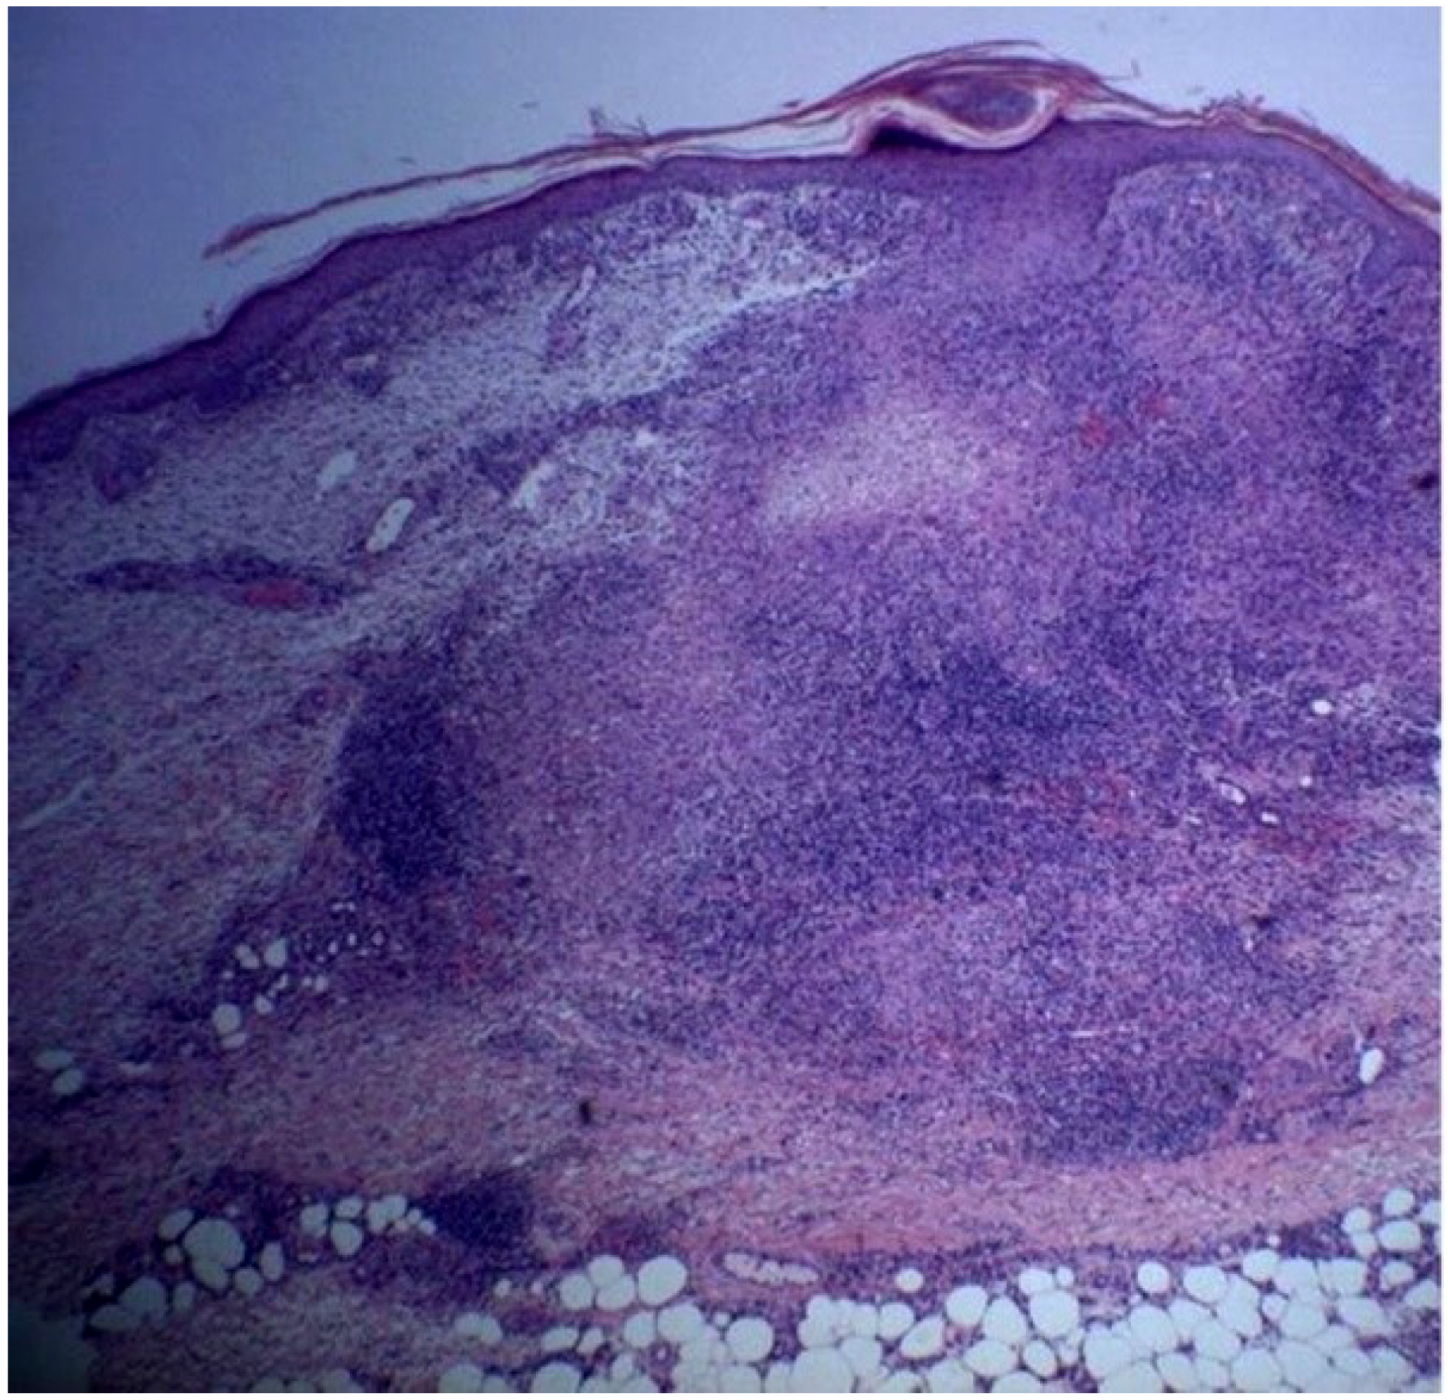

A 72 year-old women was referred to our department due to a 3-month history of a post-traumatic and slightly pruritic erythematous and exudative plaque located on her left leg. She had already been treated with several antibiotics without any clinical improvement. The patient also complained of recurrent gelatinous material extruding from the central area of the plaque. She denied any prior skin conditions or relevant medical history and had no history of recent travel. On physical examination it was observed on the anterolateral lower third of the left leg, a rounded, ill-defined erythematous plaque with 3 cm long axis, centered by small erosion covered by adherent crust (Figure 1). Around the plaque there were some discrete erythematous papules. The differential diagnosis included mycobacterial infection, subcutaneous mycosis, perforating dermatoses, pyoderma and squamous cell carcinoma. A punch biopsy was performed and the histological examination revealed a well-defined nodular infiltrate occupying the papilar and reticular dermis mainly composed of lymphocytes and histiocytes. Collagen degeneration with transepithelial elimination and multiple palisading granulomas surrounding the necrobiotic collagen were prominent (Figure 2 and Figure 3). The exposed features were highly suggestive of perforating granuloma annulare. The patient was treated with betamethasone dipropionate cream applied once daily and a complete resolution of the lesion was observed in three weeks (Figure 4).

Figure 2.

Inflammatory infiltrate composed by lymphocytes and histiocytes occupying the papilar and reticular dermis with palisading granulomas surrounding necrobiotic collagen (H&E 40×).